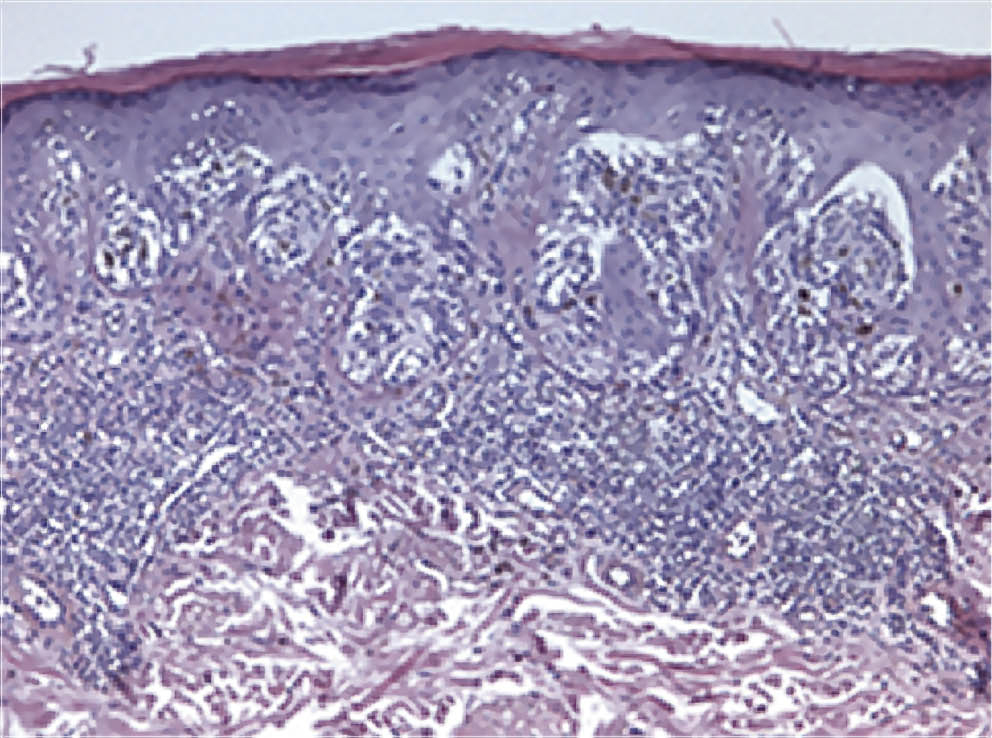

Проведена биопсия пигментного образования, при гистологическом исследовании фрагмент опухоли был представлен комплексами и одиночными меланоцитами, распространяющимися вдоль базального слоя эпидермиса, на вышележащие отделы и в сосочковый слой дермы. Клетки округлой и вытянутой формы, со светлой цитоплазмой содержали пигмент. Отмечалось распространение опухолевых клеток по ходу придатков кожи (эпителия волосяного фолликула). Опухолевые клетки с выраженным полиморфизмом, низкой митотической активностью (до 1 митоза на 1 мм2), имелись очаговые отложения глыбчатого буроватого внеклеточного пигмента, слабо и умеренно выраженная перифокальная лимфоидная инфильтрация в дерме. Признаков изъязвления, лимфоваскулярной и периневральной инвазии в пределах просмотренного материала не выявлено, имелись признаки солнечного эластоза в дерме. Морфологическая картина соответствовала лентиго-меланоме кожи (рис. 4).

Рис. 4. Морфологическая картина пигментного новообразования у пациента Б. Увеличение ×200 — клетки округлой и вытянутой формы, со светлой цитоплазмой, содержат пигмент; опухолевые клетки с выраженным полиморфизмом, с низкой митотической активностью (до 1 митоза на 1 мм2), имеются очаговые отложения глыбчатого буроватого внеклеточного пигмента; признаков изъязвления, лимфоваскулярной и периневральной инвазии в пределах просмотренного материала не выявлено; в дерме признаки солнечного эластоза / Fig. 4. The morphological picture of a melanocytic neoplasm in patient B. Magnification ×200 — cells of a round and elongated shape, with a light cytoplasm, contain pigment; tumor cells with pronounced polymorphism, with low mitotic activity (up to 1 mitosis per 1 mm2), there are focal deposits of lumpy brownish extracellular pigment; signs of ulceration, lymphovascular and perineural invasion were not identified within the examined material; in the dermis there are signs of solar elastosis